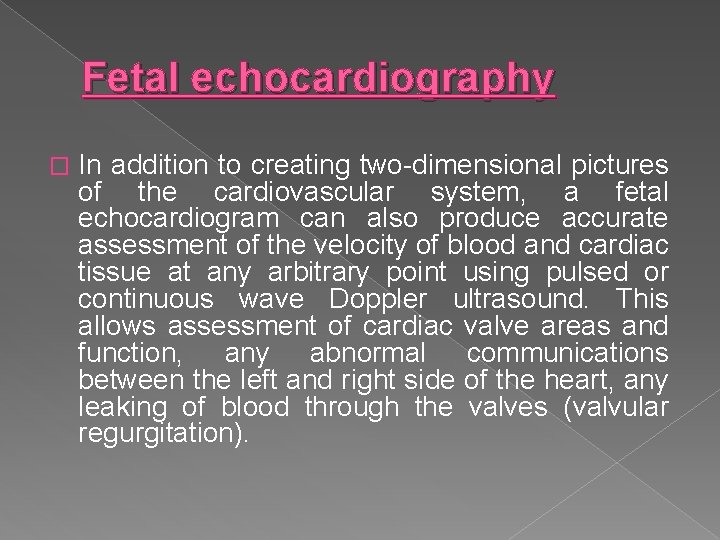

Fetal echocardiography � In addition to creating two-dimensional pictures of the cardiovascular system, a fetal echocardiogram can also produce accurate assessment of the velocity of blood and cardiac tissue at any arbitrary point using pulsed or continuous wave Doppler ultrasound. This allows assessment of cardiac valve areas and function, any abnormal communications between the left and right side of the heart, any leaking of blood through the valves (valvular regurgitation).

� Fetal Echocardiography is used to diagnose fetal cardiovascular diseases. It can provide a wealth of helpful information, including the size and shape of the heart, its pumping capacity and the location and extent of any damage to its tissues.